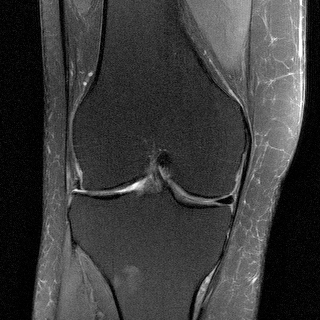

MRI

This is what an MRI image of a knee should look like—this was created using the traditional, non-AI approach from an MRI running at normal speed. The NYU / Facebook project aims to create images of this quality, but created by AI from less data. NYU School of Medicine / Facebook